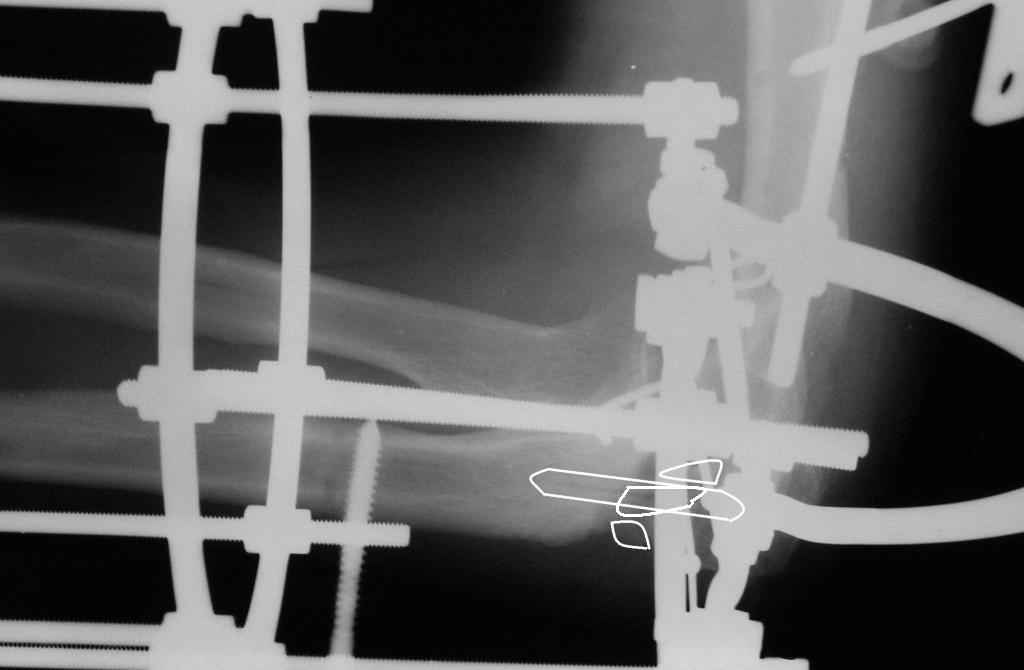

Коллеги! Сделана  операция.  Убрана  рубцовая  ткань,  освежены    концы

до  "кровяной   росы",  произведен    релиз  локтевого  отростка  и

заднего   отдела  сустава   -  прошел  до  венечного  отростка.  После

адаптации   отломков   выяснилось,  что    полное  сопоставление

происходит  только  на  1/4  периметра.   Уложены    аутотрансплантаты,

взятые  из   крыла      подвздошной    кости.  Приведена   схема.  Через

локтевой  отросток  проведены  две  спицы  с  упорными  площадками  с

разбросом  в  1  см,  закрепленные  на  отдельном  полукольце.  Дана

компрессия.  Пятые  сутки,  рана  заживает  первичным  натяжением.

Выписываю.   На   14  сутки  буду  пробовать  движения.